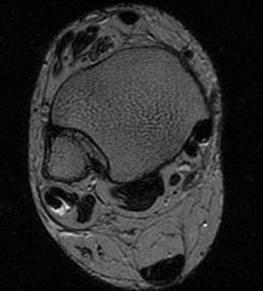

Findings

- tendonitis - fluid around tendons

- tendinopathy - tendon thickening

- tears

Tendinitis - fluid around tendon